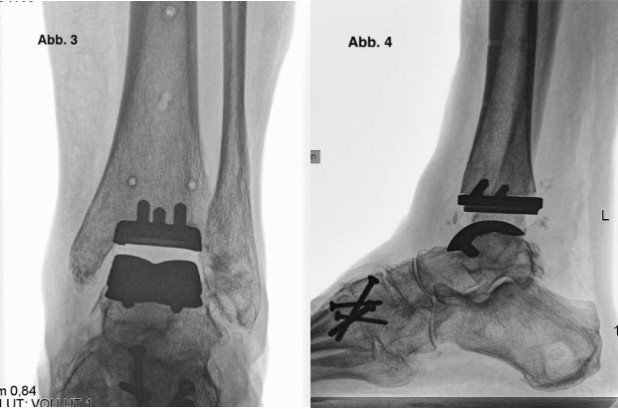

Der Eingriff liess sich plangemäss und problemlos durchführen; insbesondere gelang es, das Sprungbein gerade auszurichten und die beiden Prothesenteile zentriert zu platzieren.

Die Röntgenkontrolle nach sechs Wochen zeigte ein sehr gutes Ergebnis mit zentriertem Sitz der Prothesenkomponenten und nun gerader Stellung des Sprungbeins. Die Patientin durfte ab sofort normales Konfektionsschuhwerk tragen und nach Massgabe der Beschwerden zur Vollbelastung übergehen.

Abb. 4: Röntgenbild oberes Sprunggelenk von der Seite nach Implantation des Kunstgelenks